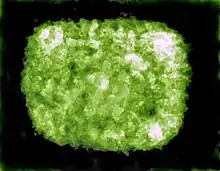

Like other viruses in the Poxviridae family, capripoxviruses are brick-shaped. Capripoxvirus virions are different than orthopoxvirus virions in that they have a more oval profile, as well as larger lateral bodies. The average size of capripoxvirions is 320 nm by 260 nm.